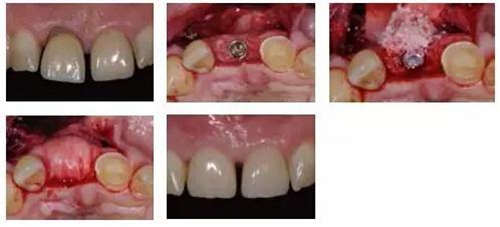

新型材料在口腔軟硬組織增量中的應(yīng)用 科貿(mào)嘉友收錄

新型材料在口腔軟硬組織增量中的應(yīng)用

引導(dǎo)骨再生技術(shù)已成為現(xiàn)代口腔種植學(xué)中被廣泛接受的治療方式,現(xiàn)已有各種各樣的材料和技術(shù)。傳統(tǒng)上使用的方法是自體骨移植,該方法會增加患者發(fā)病率以及手術(shù)困難;為避免這些問題,現(xiàn)提出了聯(lián)合使用異種異體骨替代材料和天然膠原膜的治療方法,該方法在牙種植學(xué)的引導(dǎo)骨再生中已有長達14年的成功數(shù)據(jù),被認為是擁有最多文獻記載的方法。為保證長期成功,種植體周圍健康的組織是必要前提,角化黏膜的寬度最小為2mm。與骨增量一樣,患者和臨床醫(yī)生希望使用自體組織的替代材料?,F(xiàn)在的臨床證據(jù)表明異種異體軟組織替代材料使用安全,能夠完全與周圍的組織融合,保證角化組織增量以及長達4年的穩(wěn)定的軟組織輪廓。